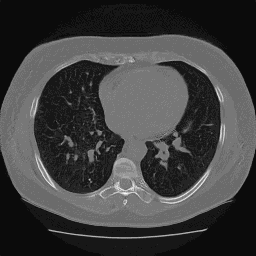

One of these is fake, and you can probably already tell which one it is.

Recently, I have been leading a small team of 3 students at Georgia Tech in a project to explore the use of generative models for privacy-preserving image generation for CT slices of patients' lungs. We are specifically participating in the ImageCLEF 2026 ImageCLEFmed GANs competition Subtask 3 "Privacy-preserving CT slice generation". In this post we will go over some exploratory data analysis on the 2025 dataset. Unfortunately, the 2026 dataset was not available at the time of presenting our results for the EDA work. We were able to acquire the 2025 data and perform some preliminary analysis with the overarching goal being to determine if the 2025 generated dataset was privacy-preserving.